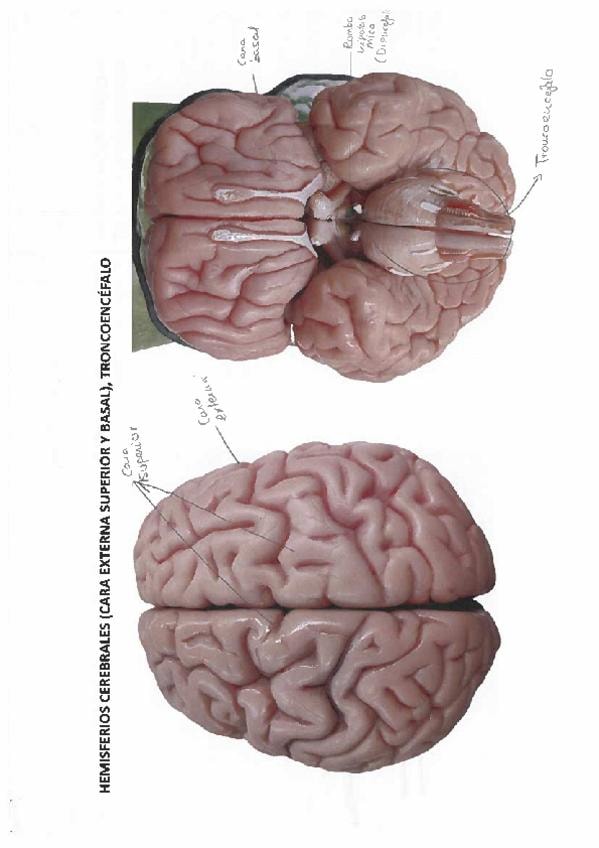

He publicado nuevos apuntes de 2º Anatomía Humana Iii: Modelos-Practicas.pdf

26 páginas